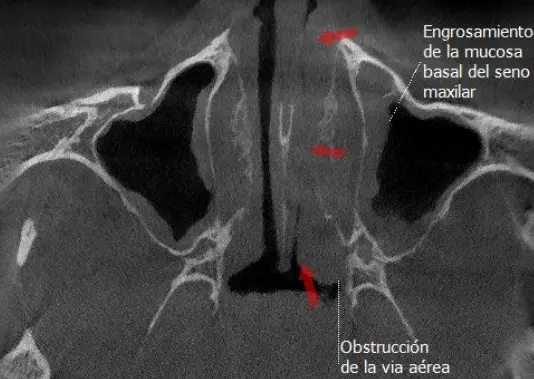

TOMOGRAFÍA PARA SENOS PARANASALES

Preciso para diagnosticar sinusitis, pólipos, obstrucciones, fracturas o tumores, ya que muestra huesos, mucosas y secreciones, y ayuda a planificar cirugías